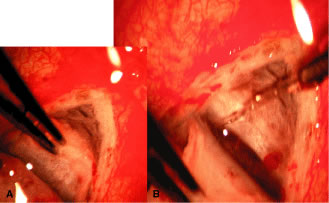

during the postoperative period. After the limbal area has been meticulously cleaned, either with a fornix-based

or a limbus-based flap, light cautery outlines the position of

the scleral flap (Fig. 15B). The shape of the flap is unimportant but in the routine case. We prefer

one that is approximately 2 mm wide circumferentially and 3 mm long

radially. This rectangular flap is easy to dissect and involves relatively

little scleral tissue. A no. 67 Beaver blade is used to incise the sclera in the area outlined

by the cautery. This incision should be at least half and preferably

two thirds the thickness of the sclera. Magnification of the operating

microscope usually is increased during the creation of the scleral flap. If the surgeon is right handed, the right-hand posterior corner of the

scleral flap is grasped with a forceps such as the Pierce-Hoskins forceps. This

instrument has indentations but no teeth and, therefore, is

not likely to penetrate or tear the scleral flap. Even in cases in which

the surgeon wishes to develop a thin scleral flap, it is preferable

to start the dissection with a thick flap, at least one half the scleral

thickness (see Fig. 13C). As the surgeon proceeds, the flap can be thinned to the proper thickness. The no. 67 Beaver blade may be used to dissect the flap. The knife should

be held as parallel to the brow as possible, because this position

facilitates dissection of the flap (see Fig. 15D). Finer, sharper “superblades” are useful when making very

small scleral flaps. The thickness of the flap must be monitored carefully as it is developed. The

surgeon should be careful never to dissect blindly but always must

see the tip of the knife. Flipping the flap forward and back, so that

the surgeon sees the outside and then the inside, can help in estimating

the thickness of the sclera. The assistant should be diligent in sponging to keep the view of the dissection

as clear as possible. We prefer to keep the scleral flap dry

rather than to irrigate it; irrigation tends to hide the landmarks at

the depth of the flap. Firm traction should be placed on the scleral flap that is being developed

so that cutting is performed against traction. The flap is extended

for at least 1 mm and preferably 2 mm anterior to the junction of the

white sclera with a clear cornea (see Fig. 15E). Once the flap has been developed, and before the anterior chamber is